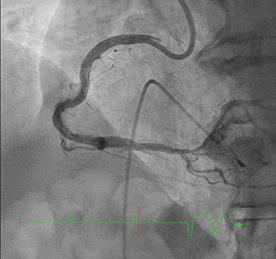

Can thiệp ngã ba động mạch liên thất trước và nhánh chéo 1 với hai stent có bọc thuốc bằng kĩ thuật cullote. Tiếp tục can thiệp động mạch vành phải với ống thông can thiệp (guiding catheter) (Cordis JR4 cm 6Fr) và dây dẫn (Asahi Sion 0.014”). Nong tổn thương bằng bóng 3.5 x 15mm (Neich Sapphire), bóng 4.0 x 12 (NC Quantum Apex), bóng cắt 3.5 x 15 (Cutting balloon, Angiosculpt) không làm vỡ được mảng vữa xơ. Quyết định dùng hệ thống khoan cắt mảng vữa xơ với dây dẫn mềm (Boston Scientific Rotablator Rotalink Plus) và mũi khoan (burr) 1.5mm. Tuy nhiên vì kích thước động mạch quá lớn nên mũi khoan đi qua tổn thương mà không chạm vào mảng vữa xơ được. Chuyển sang mũi khoan có đường kính lớn hơn 2.15mm với tốc độ khoan 150000 vòng /phút. Khi mũi khoa đi qua được 1/3 tổn thương thì không thể di chuyển được tiếp. Nhận định tại thời điểm đó là mũi khoan bị kẹt trong tổn thương tại đoạn giữa của động mạch vành phải. Ngay lập tức các bác sỹ có kinh  nghiệm can thiệp trong bệnh viện được mời đến phòng can thiệp đồng thời thông báo cho các phẫu thuật viên tim mạch chuẩn bị trong trường hợp cần thiết. Bệnh nhân có biểu hiện đau tức ngực trái, tuy nhiên mạch và huyết áp tương đối ổn định, điện tim không thay đổi. Dòng chảy trong động mạch vành còn duy trì nhưng chậm TIMI 2. Sau khi hội ý, hướng xử trí đầu tiên là dùng dây dẫn cứng Conquest Pro (Asahi) để đi qua tổn thương nhưng không thành công. Sau đó chúng tôi quyết định cắt đoạn đầu của hệ thống nối mũi khoan, đưa ống thông heartrail (Terumo) sát vào mũi khoan nhằm thay đổi tư thế và cố định mũi khoan vào dây dẫn để đưa ra ngoài. Cuối cùng mũi khoan được đưa ra ngoài thành công. Tổn thương tiếp tục được nong bằng bóng cắt và bóng áp lực cao và đặt được giá đỡ kim loại (stent) bọc thuốc 4.0 x 26mm. Kết quả là động mạch vành được mở rộng hoàn toàn, bệnh nhân không còn đau ngực, huyết động ổn định.

Hình 1: A- hình ảnh động mạch vành trước can thiệp; B - dùng bóng cắt (cutting balloon) không phá vỡ được cấu trúc mảng vữa xơ; C – mũi khoan 1.5 không chạm vào được mảng vữa xơ vôi hóa; D – mũi khoan 2.15 bị tắc tại vị trí hẹp.